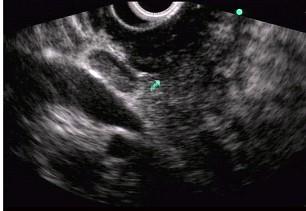

问题 男性,50岁,上腹隐痛,食欲不振3个月。1个月来出现黄疸且进行性加深,体重明显减轻,查体全身明显黄染,肝未触及,深吸气时可触到肿大胆囊底部,无触痛。化验血胆红素15mg/dl,尿检胆红素阳性图中胰腺病变可能的诊断是 ( )

选项 A.正常 B.胰腺囊肿 C.慢性胰腺炎 D.胰腺囊腺癌 E.胰腺癌

答案 E